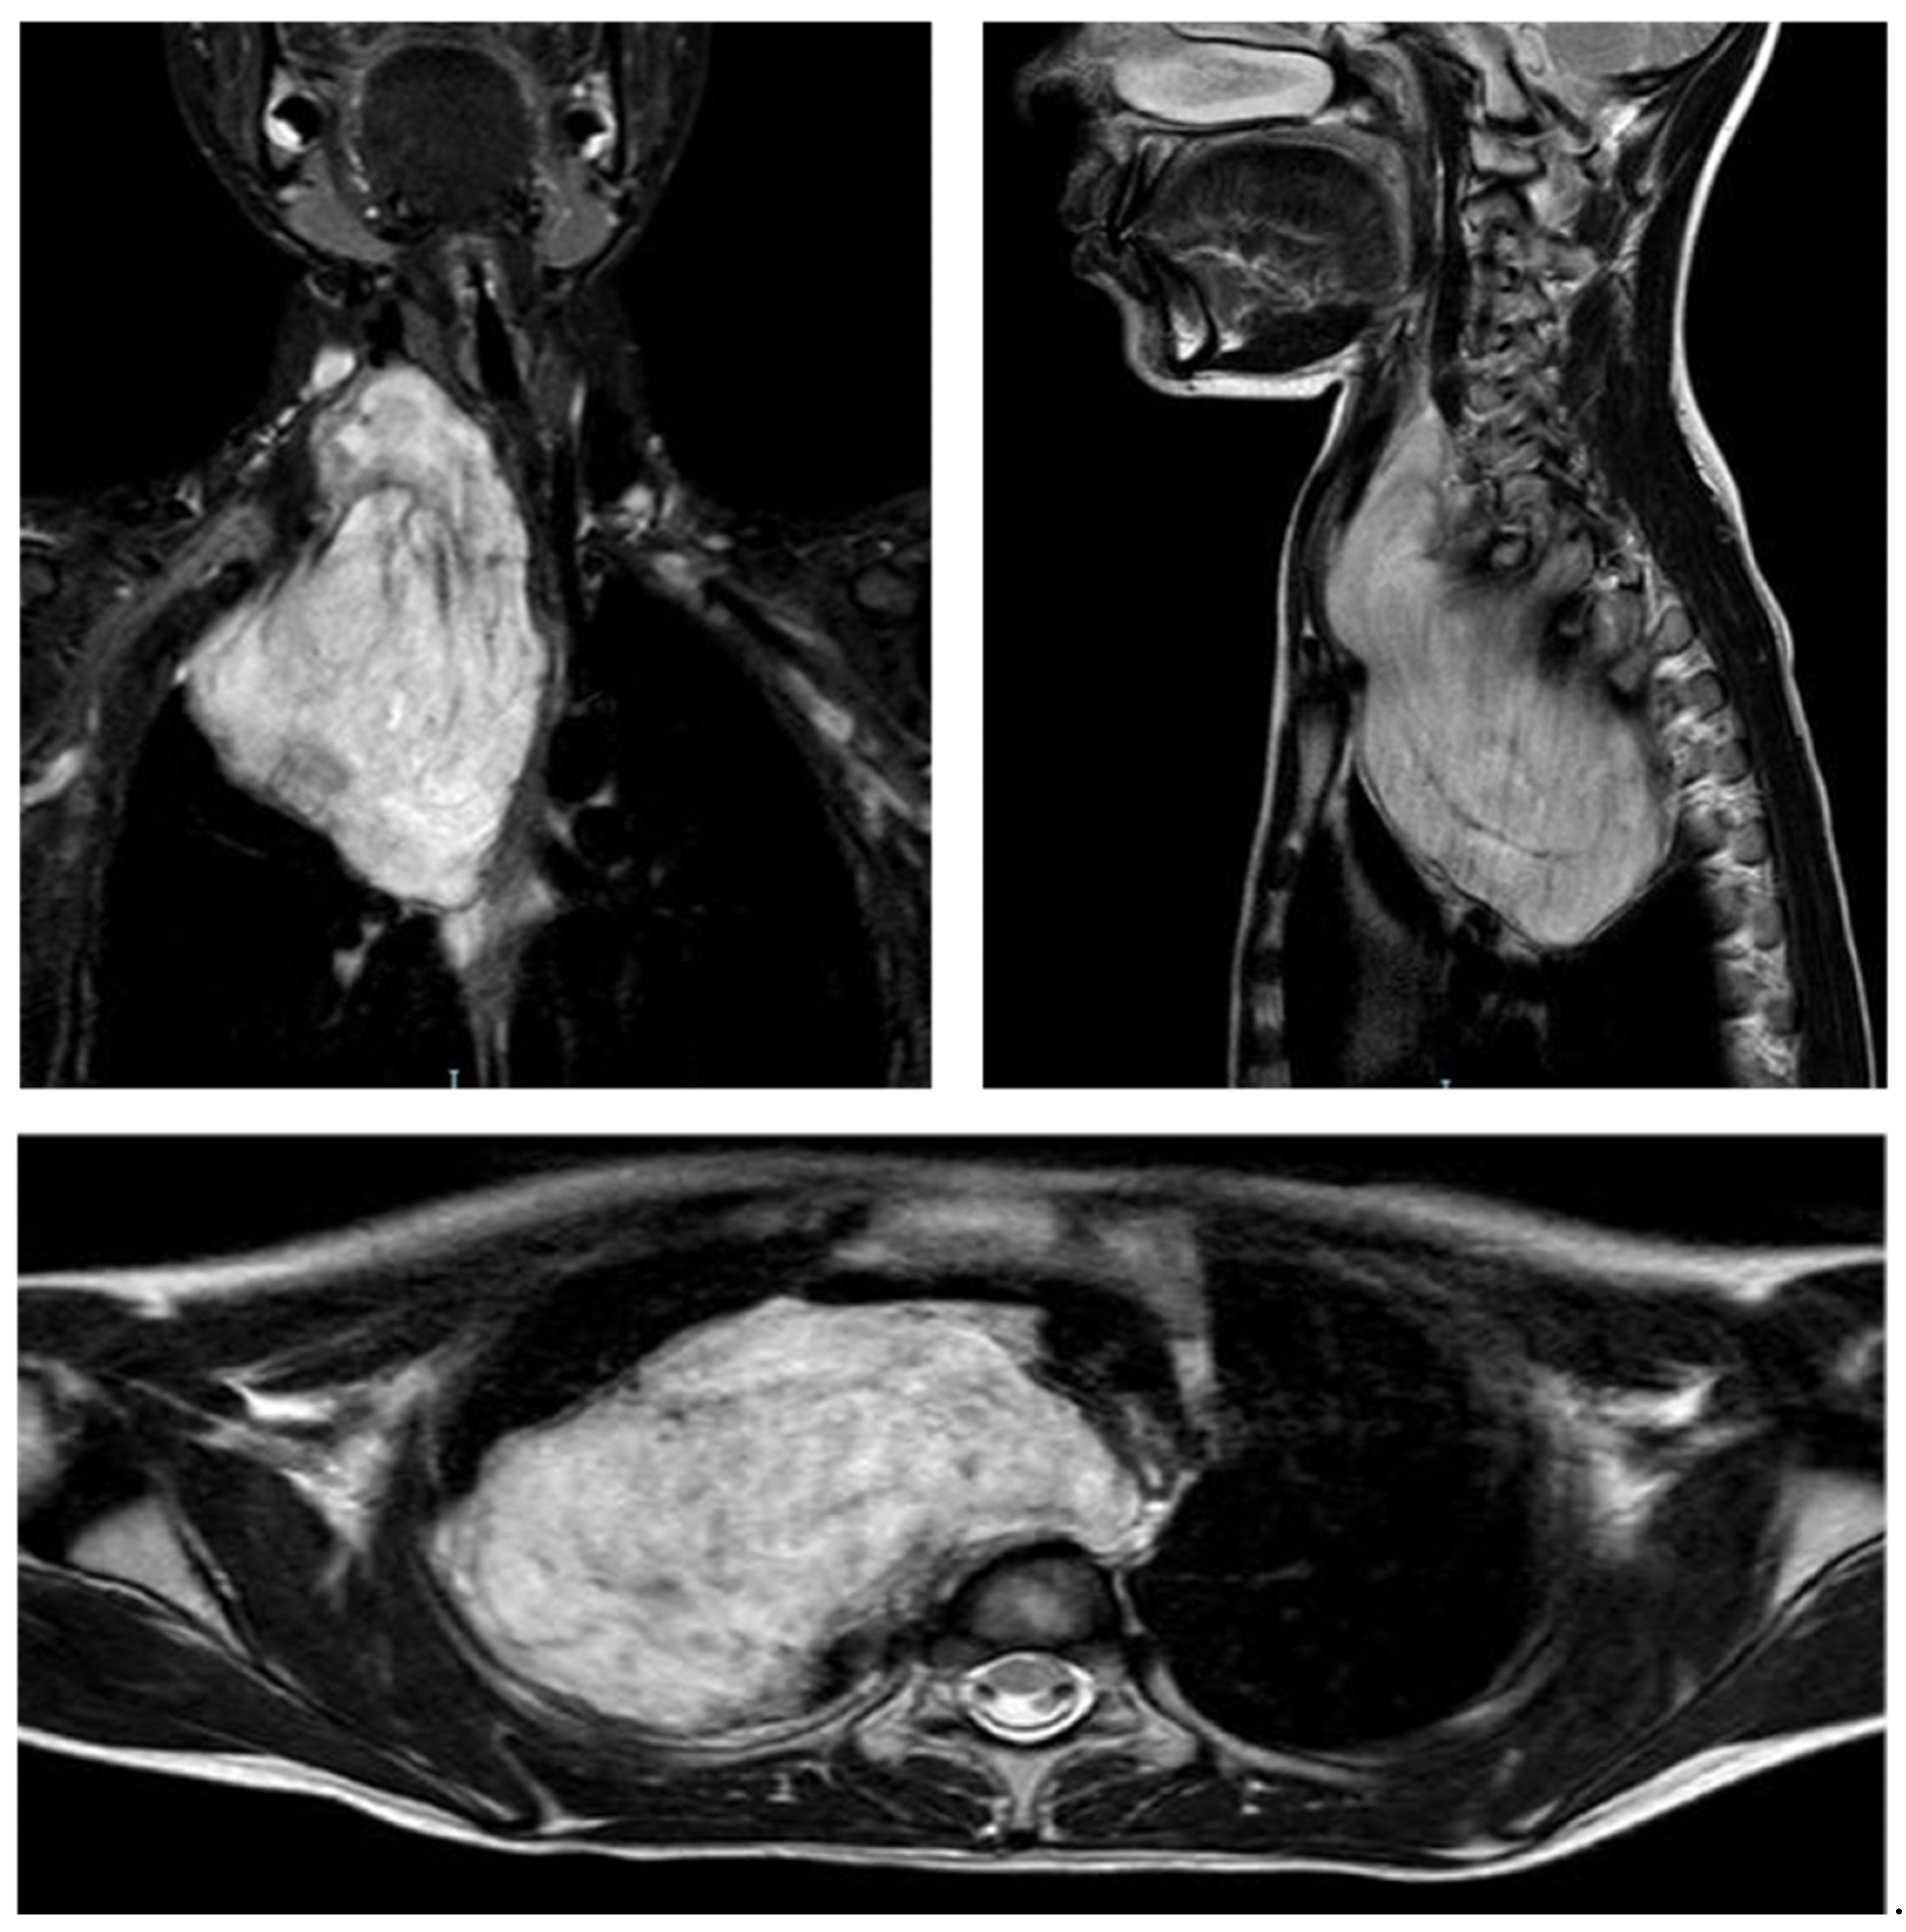

The Cervico-Parasternal Thoracotomy (CPT): A New Surgical Approach for the Resection of Cervicothoracic Neuroblastomas

2. Description of the Operative Technique